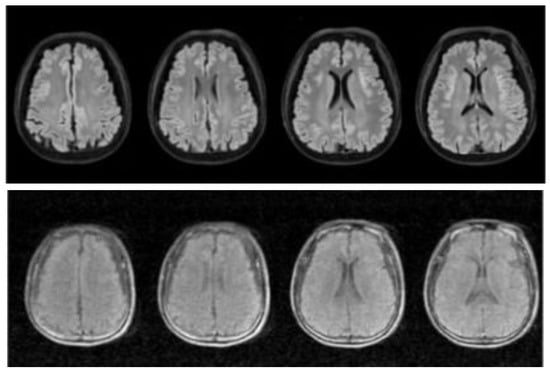

In Section 2.1, for MRI imaging technology, we introduce the advantages. However, MRI scanners rely on complex superconducting electromagnets and excellent electronic equipment for imaging, which leads to high cost, a large area of site occupancy, and demanding imaging site conditions. Therefore, people have begun to promote the development of low-cost MRI technology with ultralow field (ULF) intensity for large-scale medical image detection [53,54], which leads the MRI images’ disadvantage in that most clinical images are lost to computers [55]. Figure 1, Figure 2 and Figure 3 show the differences between T1-weighted images, T2-weighted images, and FLAIR-weighted images based on a high magnetic field, standard MRI images, and an ultralow field MRI, respectively. It can be seen from the comparison that these ultralow field MRI images have low brightness, poor contrast, no obvious details, and considerable noise, which is not convenient for computer and doctor detection.

Figure 3.

The top image is taken from the T2W strong magnetic field, and the bottom image is taken from the T2W weak magnetic field in the same position from left to right.